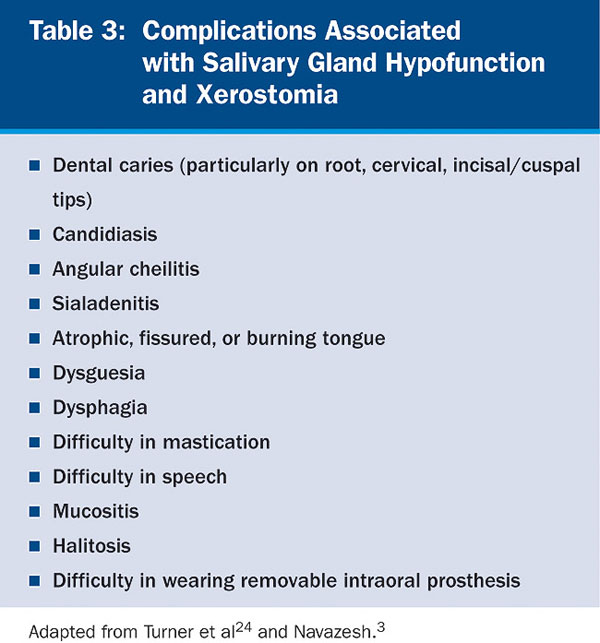

Saliva aids for oral cavity cleansing, swallowing, taste, speech, and digestion could be compromised in patients with salivary gland hypofunction. The oral mucosa may appear dry and friable. The tongue may appear dry and fissured (Figure 1). Dental caries, plaque accumulation, gingivitis, and periodontitis are common in patients with significant salivary gland hypofunction (Figure 2). Infections, such as oral candidiasis (Figure 3), and enlargement of salivary glands from sialadenitis are seen commonly in patients with moderate-to-severe salivary gland hypofunction (Figure 4). Difficulty in mastication and swallowing also may indicate advanced salivary gland hypofunction19 and can contribute to poor nutrition.20 Denture retention may become difficult because of the lack of saliva12 (Table 3).